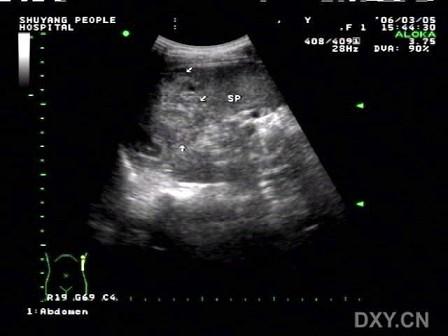

问题 图为外伤后伤者脾脏图像,诊断为?(?)

选项 A.中央型脾破裂 B.真性脾破裂 C.包膜下血肿 D.脾肿瘤 E.脾梗死

答案 B